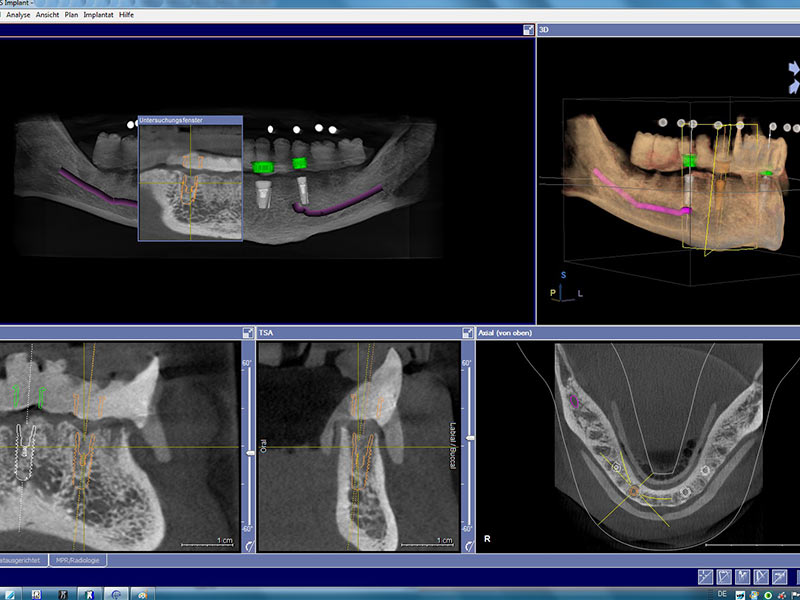

Zahnimplantate werden anhand von moderner virtueller 3D-Planung passgenau geplant und inseriert. Der Vorteil von Implantaten besteht darin, dass festsitzender ästhetischer Zahnersatz auch in solchen Fällen realisiert werden kann, in denen sonst nur herausnehmbare Prothesen möglich wären. Zudem ist im Gegensatz zur Brückenprothetik kein Beschleifen der Nachbarzähne notwendig.